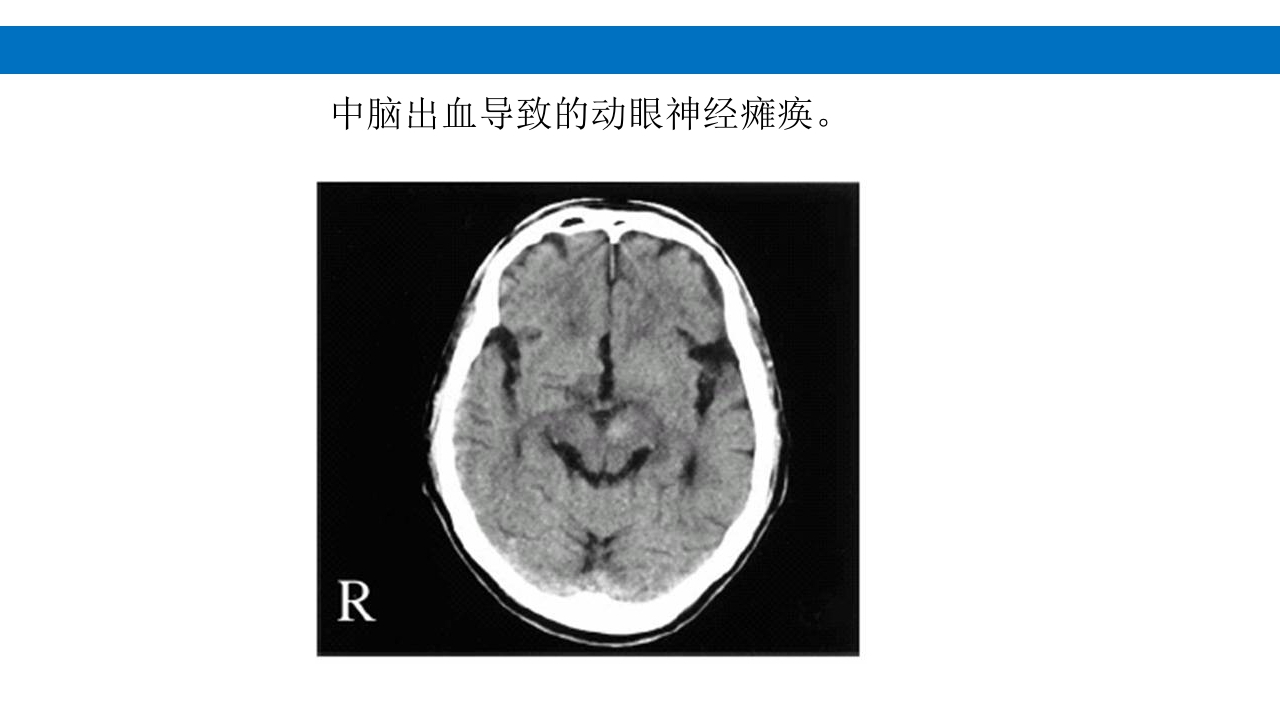

颅脑损伤的并发症及后遗症 讲解人:xxx 20XX年x月x日 1.颅骨骨髓炎 病因:为头皮软组织、中耳、乳突和副鼻窦等处炎性感染而经导 血管侵入颅骨内或颅脑开放伤感染所引起,亦可由菌血症后发生 的细菌栓子由血运转移至颅骨内。 影像学表现: 头部CT: 1.表现为不规则的蜂窝状骨质破坏区,主要位于板障,亦可累 及内外板。 2.破坏区内可见高密度的米粒状细小的高密度死骨。 3.周边可见骨质硬化增生,颅板外无骨膜反应。 4.局部的头皮可见软组织肿胀。 头部MRI: 由于受累部位细胞成分和水量增多,T1WI为低信号, T2WI为高信号,急性期边界不清,慢性期病灶局限, 边界清晰。MRI显示骨质破坏没有CT效果好。 治疗: 除应用抗菌药物控制感染外,当感染局限或已有死骨形成后, 应行手术切除感染...